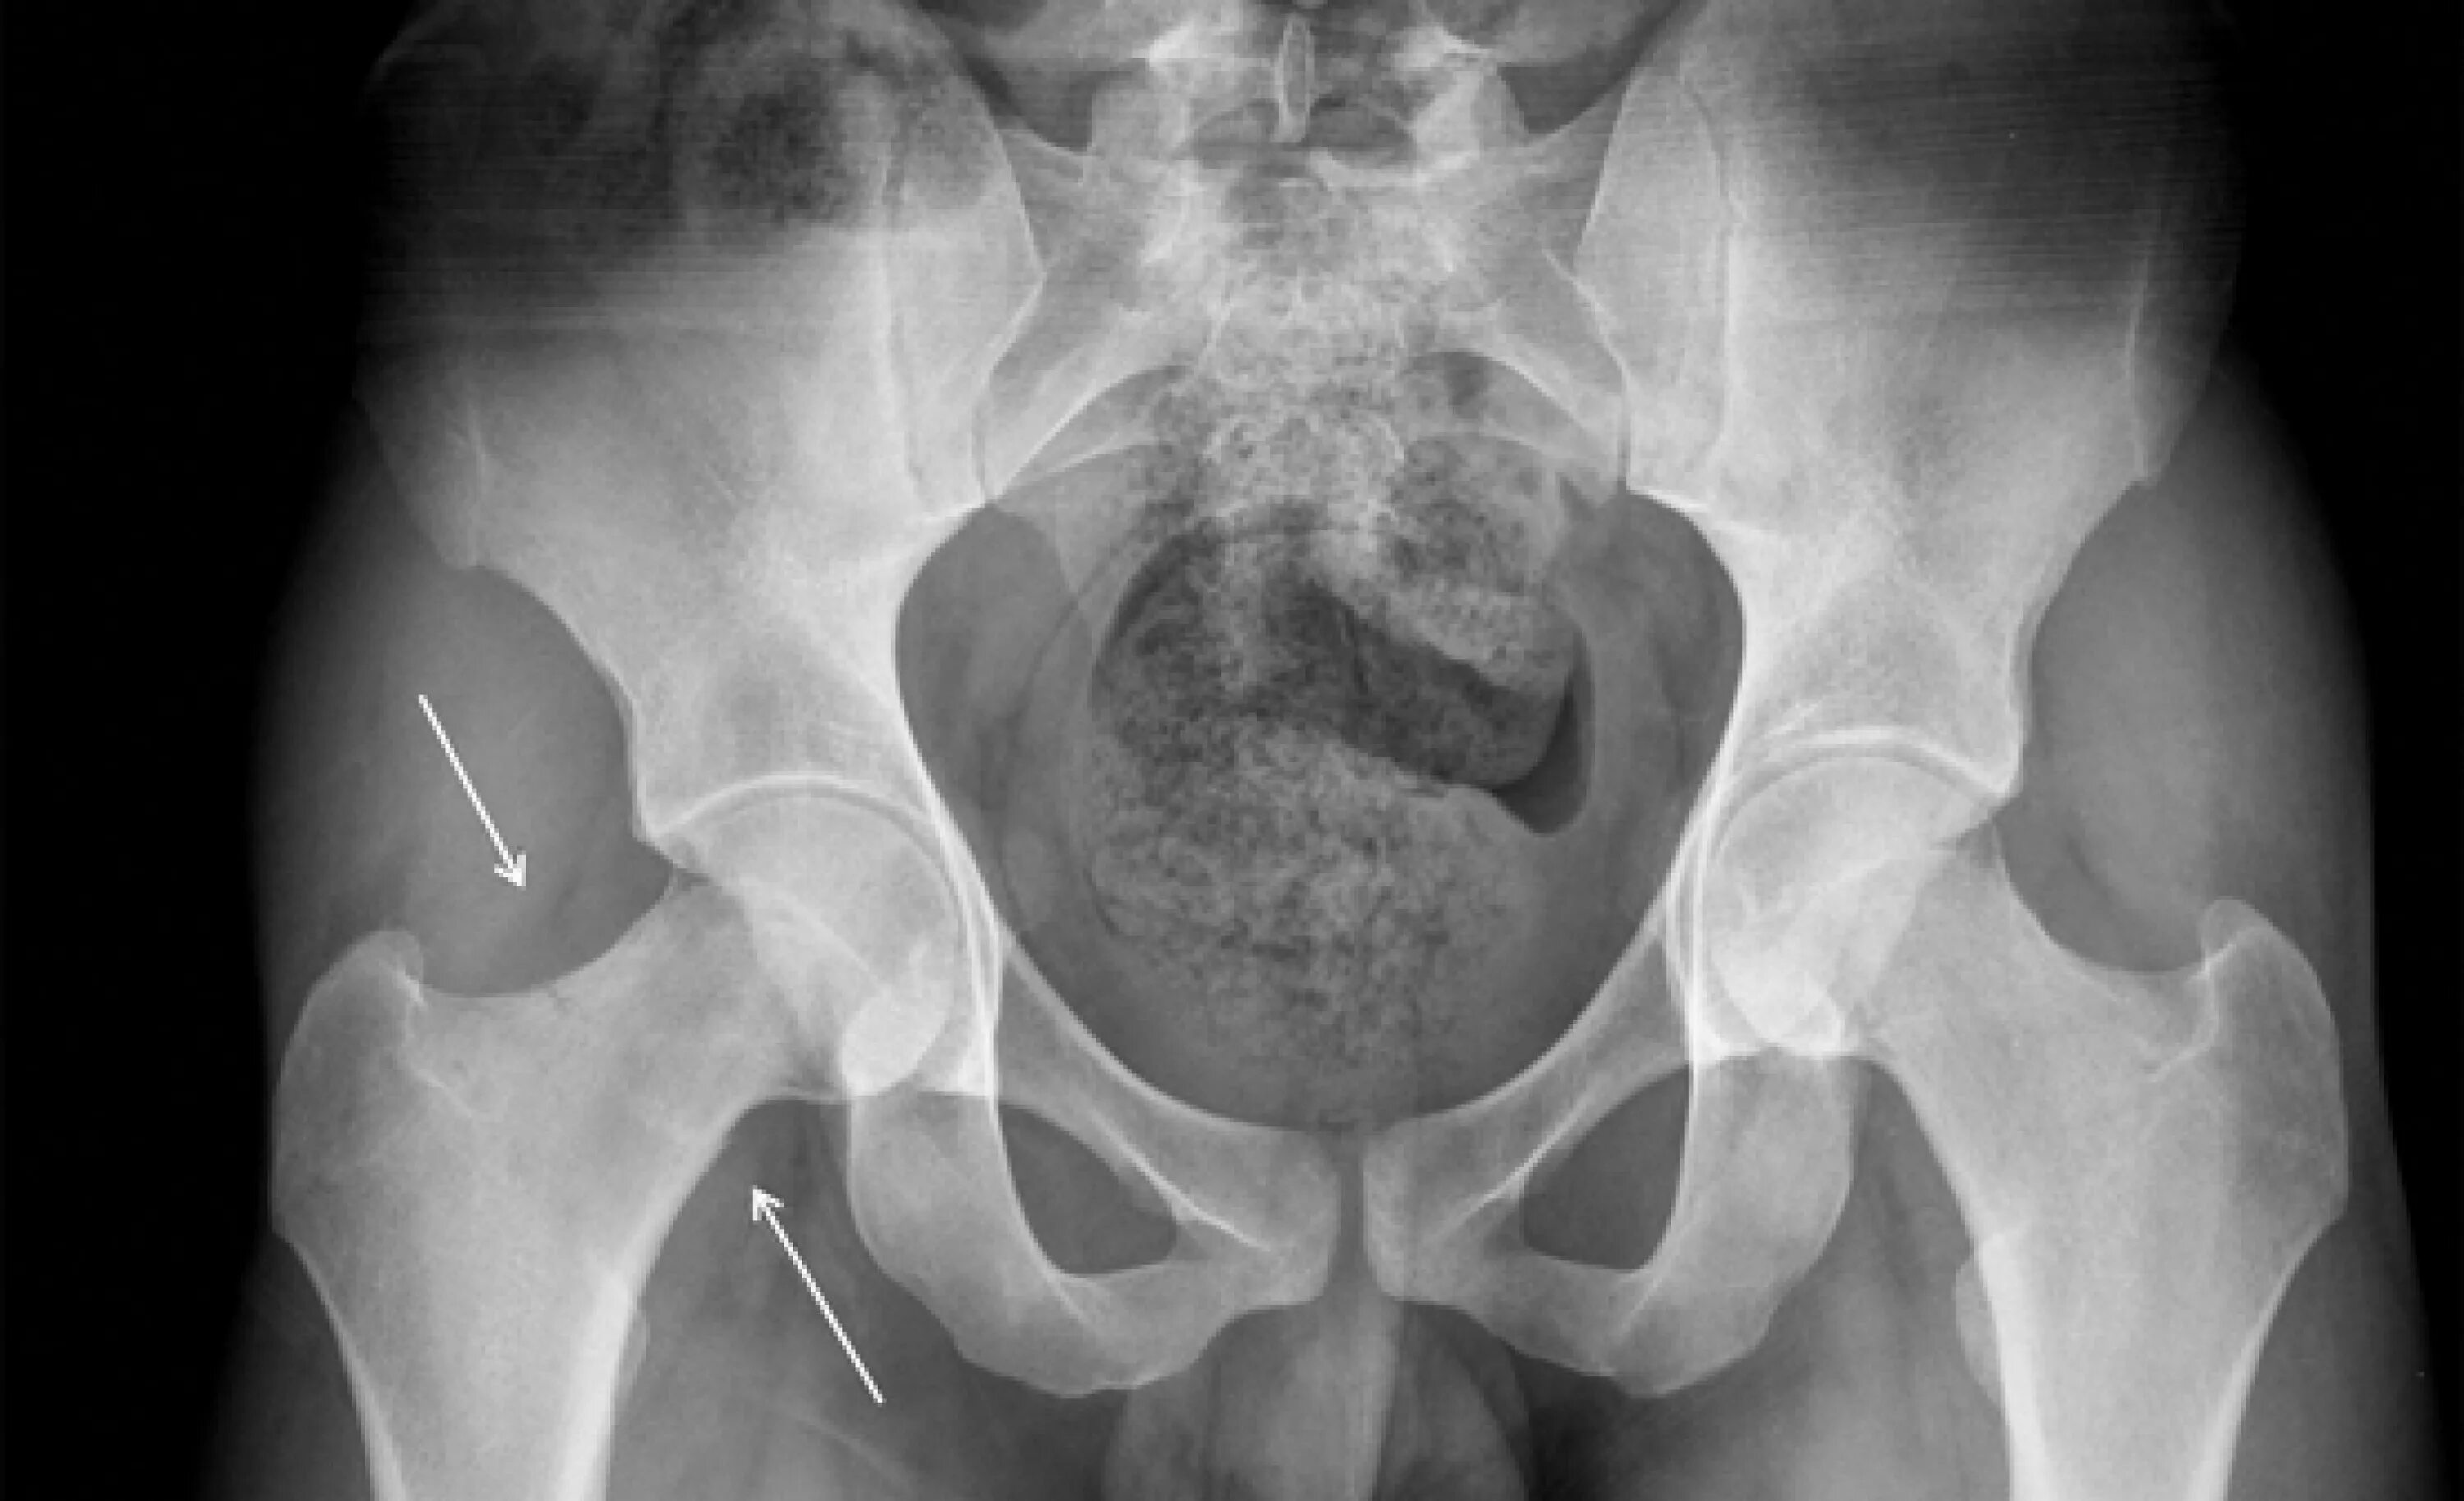

Перелом 1 3 бедра